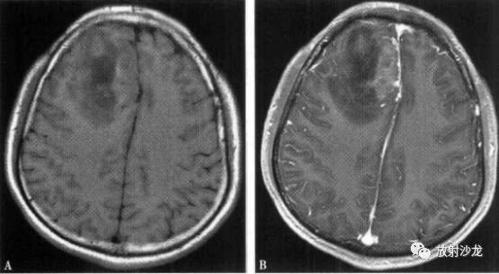

明显强化主要见于脑外肿瘤和胶质母细胞瘤.

影像总结丨脑膜三件套——脑膜瘤,hpc/sft